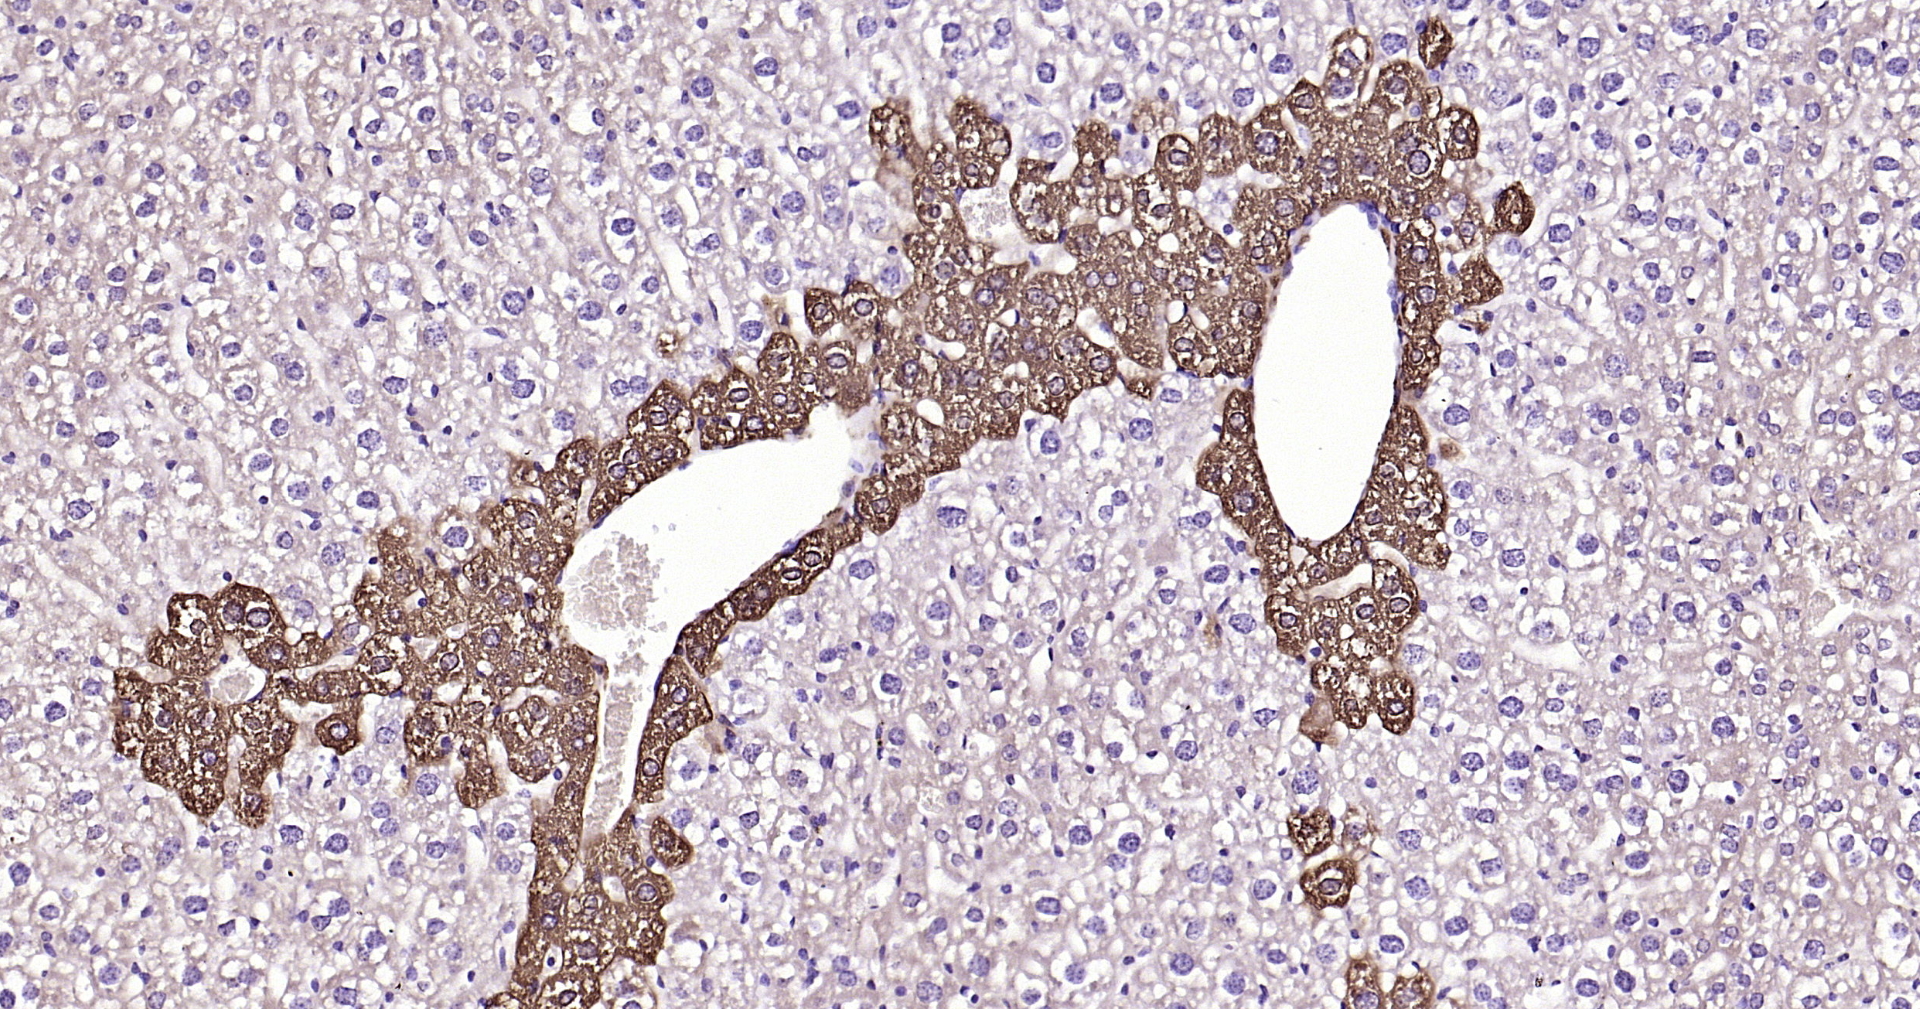

• IHC-P

• IF(IHC-P)

IHC-P IHC-P1:50-200

IF(IHC-P) IFIHC-P1:50-200